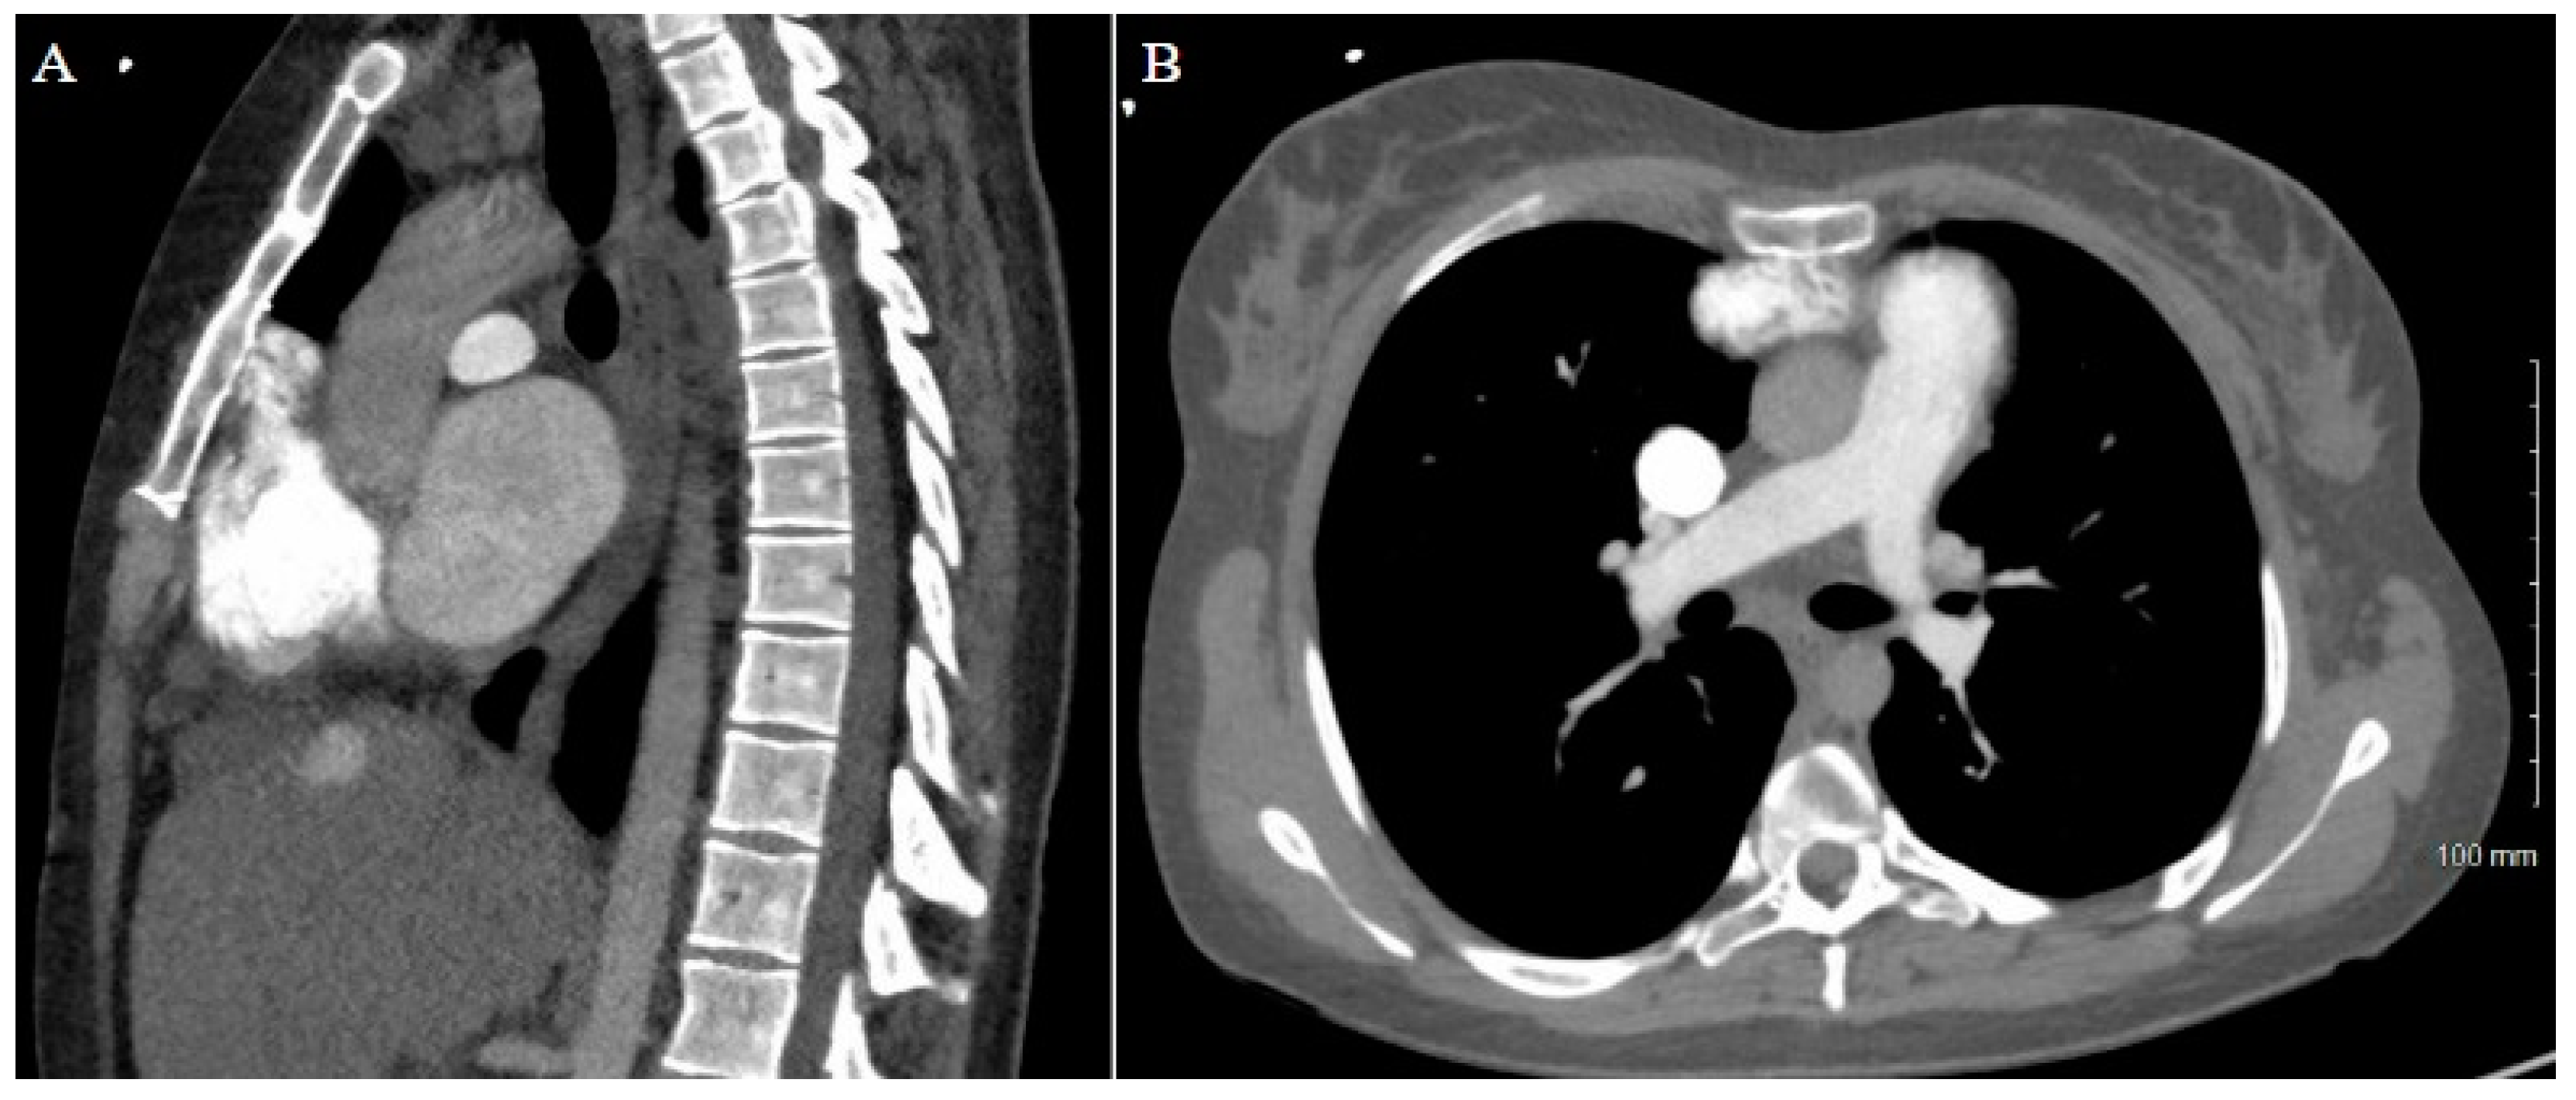

As expected, the patient’s extensive history of cardiac surgery with three prior sternotomies made for a complicated reentry to the thorax. A review of the preoperative chest CT demonstrated tight adhesions between the LVAD outflow graft and the superior retrosternal surface (Figure 1). The precise anatomic level of these adhesions and the safe portion of the sternum without adhesions was localized by leveraging the sternotomy wires as landmarks. Intraoperatively, a partial sternotomy was made from the xiphoid process, inferiorly, until the third intercostal space (Figure 2A). At this point, the outflow graft was mobilized, and aortic cannulation was established via the LVAD outflow graft, and IVC drainage was established via percutaneous peripheral femoral vein access. The inferior portion of the sternum was then carefully dissected away from the heart, mediastinum, and LVAD outflow graft. Due to dense adhesions between the LVAD outflow graft and the sternum, a section of periosteum was left attached to the graft.

Figure 1. Patient 1 CT chest. (A) Sagittal view and (B) axial view reveal extensive adhesions between LVAD outflow graft and superior retrosternum. (C) 3D reconstruction with labeled structures LVAD outflow graft (a), sternum (b), ascending aorta (c), aortic arch (d), and descending aorta (e) highlighting the point of maximal LVAD graft–sternal contact (white arrow).

A careful review of the CT imaging was crucial to the preoperative planning of both cases of stepwise sternotomy. The preoperative imaging identified not only structures at risk of reentry injury but also the specific site at which this risk was present. By utilizing landmarks identified in the imaging, we were able to formulate an individualized two-stage approach to reentry that was safe for each patient. With one patient demonstrating inferior retrosternal adhesions and one demonstrating superior retrosternal adhesions, understanding this patient-specific anatomy was necessary to strategize a safe approach to stepwise sternotomy.